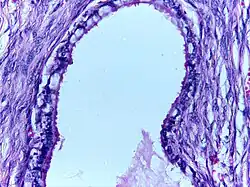

Serous cystadenoma | Histopathology of serous cystadenoma, with admixed scattered ciliated cells. This case closely resembles normal surface endometrial epithelium of the uterus | Category: Histopathology of ovarian serous cystadenoma | Ovarian cystadenoma |

![]() |